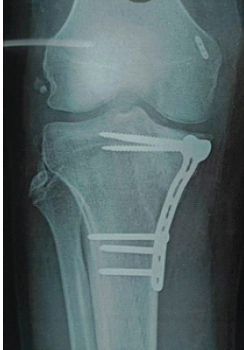

Management of a Rare Combined Osseoligamentous Knee Injury: Tibial Plateau Fracture with High-Grade Posterior Cruciate Ligament Tear Treated by Arthroscopic Reconstruction and Osteosynthesis – A Case Report

M Vivekkumar , Muthukannan Hari Sivanandan , Narendran Pushpasekaran , I Shebin Christin , M Monish Kumar , Anushka Bakshi

………………………………p.38-43